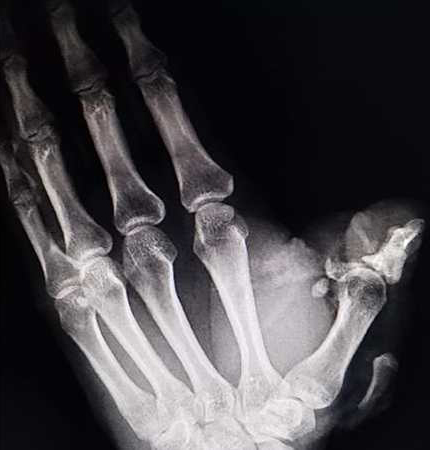

8月26日中午1時左右,我院急診醫(yī)學科收治一名由外院輾轉至我院的“左拇指創(chuàng)傷性切割”患者,該患者在工作中左手不慎被電鋸鋸傷,左手拇指畸形,傷口活動性噴血,遠端組織離斷,局部組織毀損嚴重,手指活動障礙,遠端肢體蒼白無血運。患者萬分焦慮,神情痛苦,情況不容樂觀。

急診醫(yī)學科手外傷團隊副主任劉路培、何居璘醫(yī)生立即到位,經了解患者早上8點左右受傷,急忙趕到外院尋求幫助,因傷指毀損嚴重、治療難度大、再植成活力低,首診醫(yī)院建議轉到治療條件好、救治水平高的柳州市人民醫(yī)院就醫(yī)。患者輾轉來到我院已經是中午1點多,由于受傷時間長,患者對治療逐漸失去了信心。兩名醫(yī)師查看病人的情況后,判斷這種嚴重毀損的拇指撕脫離斷傷,唯一可能恢復拇指功能的救治措施只有盡早再植,離斷拇指越早手術,再植成功的幾率就越大。為了病人,必須與時間賽跑,劉路培馬上聯系手術室團隊開啟急診綠色通道,同時進行術前準備,組織急診醫(yī)學科專家制定最佳手術方案后,立即將患者送入手術室進行急診斷肢再植術。

患者實施麻醉后,劉路培、何居璘立即在顯微鏡下為患者的傷指進行精細清創(chuàng),術中見患者創(chuàng)面嚴重污染,近節(jié)指骨及皮膚軟組織毀損嚴重伴大面積皮膚撕脫,作為一名手外科醫(yī)生,劉路培、何居璘接觸過太多諸如此類的病例,顯然這次的艱難程度遠遠超出以往。他們深知手指對于每個人而言有多重要,拇指功能的殘缺不僅影響患者的工作生活,也會打擊患者內心,常常感到自卑,所以整個團隊同心協力要保住患者的拇指。專家團隊默契配合,根據患者傷指條件術中再次調整手術方案,首先處理指骨缺損,用殘存的骨頭拼接恢復指骨的骨量,復位骨折,然后用微型鋼針小心的將骨頭固定起來,恢復了拇指的力線與角度,緊接著在顯微鏡下用比發(fā)絲還細的顯微血管縫線吻合指背靜脈、指固有動脈及神經,最后處理撕脫皮膚,一針一線都是那么仔細、完美。松止血帶后離斷拇指終于又恢復了正常血運,拇指顏色由蒼白變成紅潤、血運良好!手術順利結束,患者安全送回病房。

無獨有偶,同樣揪心的意外發(fā)生在一名年齡僅1歲7個月的患兒身上。8月30日17時,一對父母懷抱著一名男性兒童從外地趕到急診醫(yī)學科,患兒右手被門夾傷,流血5小時,在當地醫(yī)院就診,奈何醫(yī)療條件有限,為進一步診治,慕名趕到我院就診。患兒哭鬧不止,年輕父母不知所措,愁容滿面。

急診預檢分診第一時間協助醫(yī)生予患兒加壓包扎,同時通知副主任劉路培和何居璘醫(yī)生,查看到患兒手指有活動性出血,右手環(huán)指不能活動,環(huán)指末節(jié)中段不全斷離,指甲遠節(jié)斷裂。作為一名醫(yī)師同時也是父親,劉路培感同身受,非常揪心,立即啟動急診綠色通道,各部門醫(yī)護人員團結協作,患兒從預檢分診處置到送達手術室開始手術,不到1小時,“急救一體化”的高效率為患兒爭取了寶貴的黃金時間。

由于患兒年幼,血管精細,手術難度更上一層,手術團隊暗下決心:一定還給父母一個完好如初的孩子。術中顯微鏡下探查縫合側指固有動脈1條,固有神經2條,予0.6mm克氏針縱行貫穿固定指骨骨折,修復甲床及創(chuàng)面。整個術程注意力高度集中,容不得一絲馬虎。終于,離斷手指完好復位,指體飽滿,血運良好。大家都開心的笑了,手術圓滿成功就是對醫(yī)護人員最好的獎勵。

“感謝急診醫(yī)學科,感謝柳州市人民醫(yī)院”這是患者及家屬對急診醫(yī)學科最好的贊揚。作為科室負責人,甘濤每日都會帶領醫(yī)護團隊查看患者,經過醫(yī)護團隊的精心治療與護理,兩名患者術后傷指顏色紅潤、皮膚溫暖,肢端皮膚感覺恢復良好,均于近日出院。患者及家屬對我院急診急救快速、高效、高質量的服務贊不絕口。從救治高難度的斷指病人,以及低齡的斷指幼兒,急診醫(yī)學科積累了豐富的經驗,充分體現我院在手外傷治療的整體實力及救治能力。